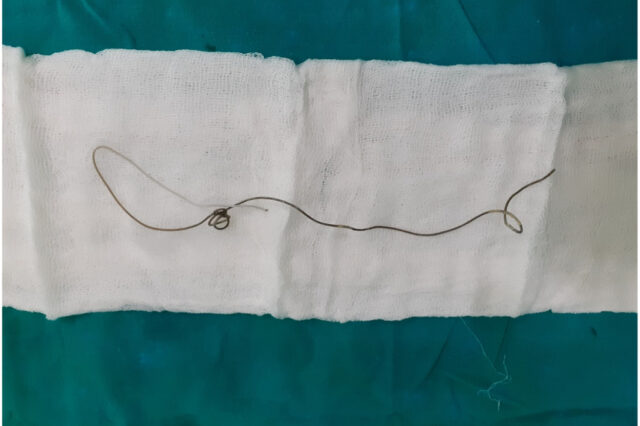

Περίπου 20 εκατοστά ήταν το καλώδιο που αφαίρεσαν οι γιατροί από το πέος ενός 17χρονου στη Σρι Λάνκα.

Η διαδικασία αφαίρεσης του καλωδίου από το πέος

Οι γιατροί του νοσοκομείου για να αφαιρέσουν το καλώδιο υπέβαλλαν τον 17χρονο σε κυστεοσκόπηση με γενική αναισθησία.

Σύμφωνα με όσα αναφέρει η επιστημονική επιθεώρηση, δεν υπήρξαν μετεγχειρητικές επιπλοκές.

Στην επιστημονική βιβλιογραφία περιγράφονται αρκετές εκδηλώσεις πολυεμβολοκοιλομανίαςμε αντικείμενα που εισάγονται στην ουρήθρα, όπως μολύβια, θερμόμετρα, ηλεκτρικά καλώδια, σύρματα κ.ά., τα οποία φυσικά είναι επικίνδυνα.